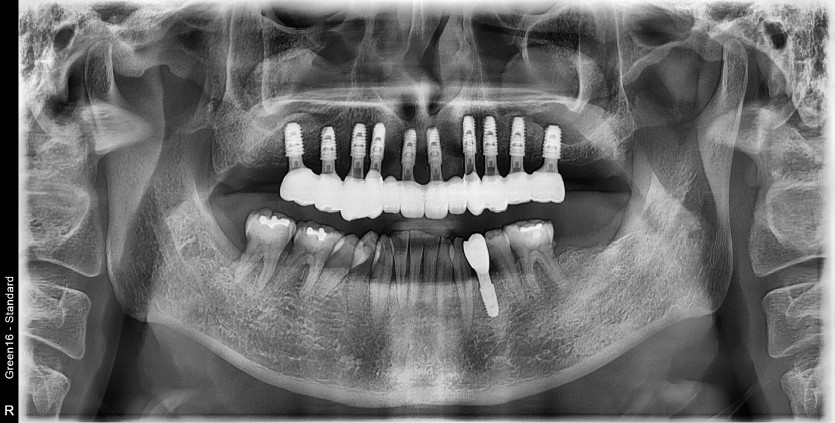

만 45세 상악 전체 임플란트 증례

상악 전체 임플란트 증례입니다.

10개의 임플란트로 완성하였습니다.